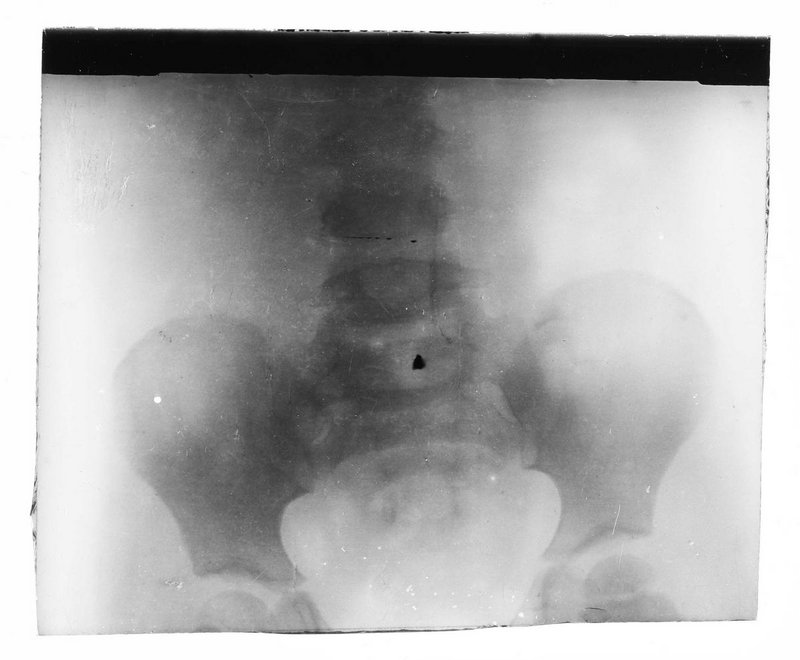

Robert Kienböck

AT-MUW-FO-000101-0030

Medizinisches Fachgebiet

Radiologie

Fotografie (FO)

S/W, Glasdiapositiv

um 1896

Wien

Bildmaß 8,3 x 9,7 cm